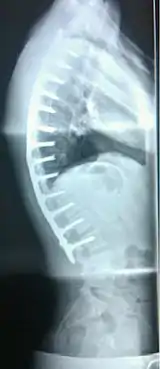

A pre-operative image of a 22-year-old male with a very extreme case of Scheuermann's disease

A 20-year-old male with Scheuermann's disease, showing various measurement of kyphotic/lordotic degrees and their supplementary angles. Notice the signature 'wedging' shape of the four vertebrae in the lower thoracic area. The other vertebral bodies are otherwise normal. The measured kyphosis for this patient is ~70°.